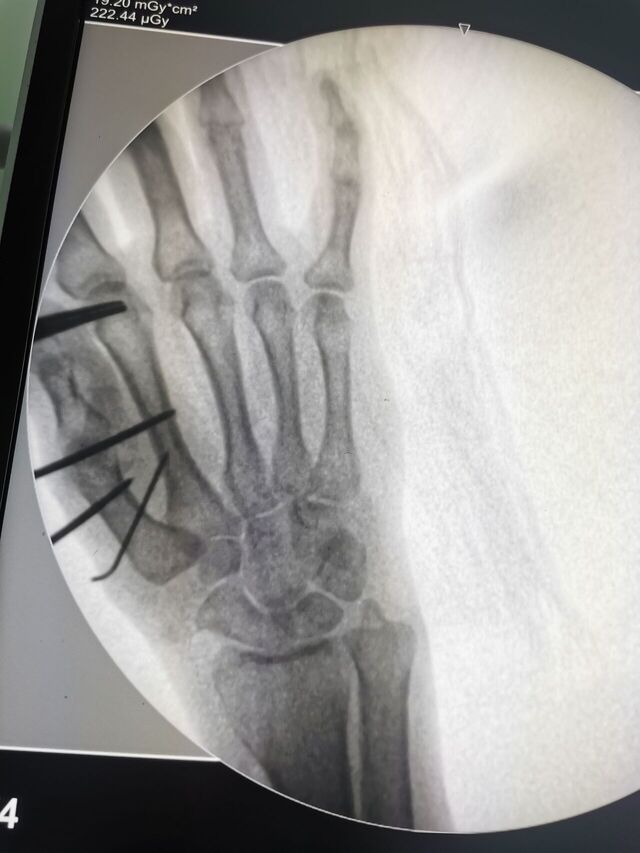

CMC关节炎

大多角骨切除韧带重建术

IMG_20250414_122627.jpg

IMG_20250414_122644.jpg

IMG_20250415_152232.jpg